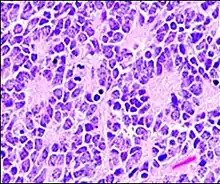

A Homer-Wright pseudorosette is a type of pseudorosette in which differentiated tumor cells surround the neuropil.[15] Examples of tumors containing these are neuroblastoma, medulloblastoma, pinealoblastoma, and primitive neuroectodermal tumors of bone. Homer-Wright rosettes are considered "pseudo" in the sense that they are not true rosettes. Unlike Flexner–Wintersteiner rosettes, which contain an empty lumen, Homer-Wright rosettes contain abundant fibrillary material. They are named for James Homer Wright.

Structure of a Homer-Wright pseudorosette